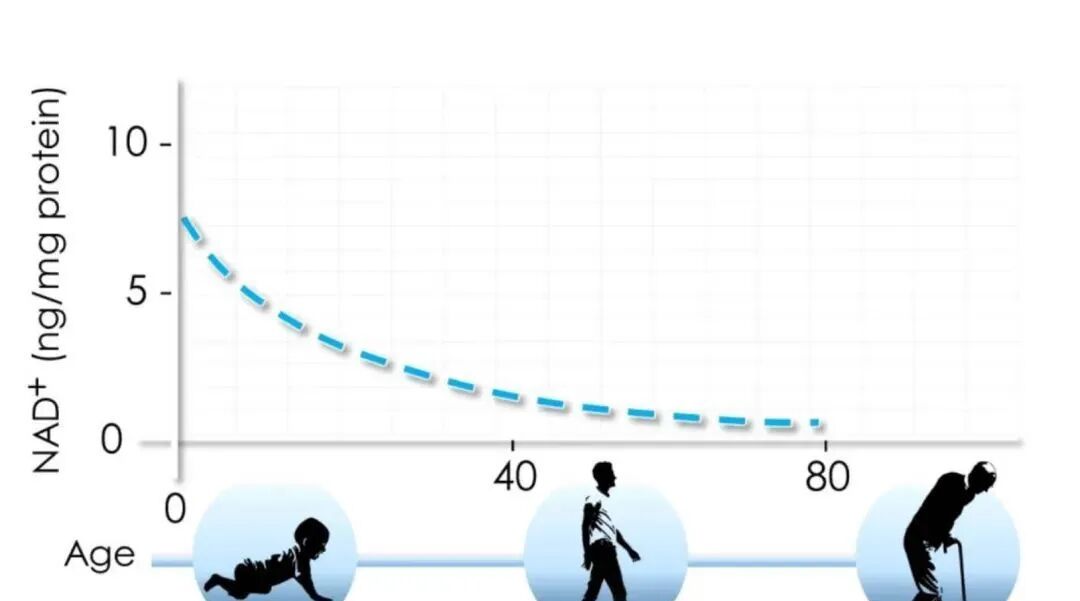

What is NAD+? NAD (also known as nicotinamide adenine dinucleotide ) is a crucial molecule in human cell metabolism and various reactions. Since its discovery in the early 18th century, scientists have recognized its significance. Without NAD, many

Among the thousands of coenzymes in the human body, NAD+ holds the top position and is known in the medical field as the "number one coenzyme" of the human body. Participates in thousands of physiological reactions, controlling cell repair, energy